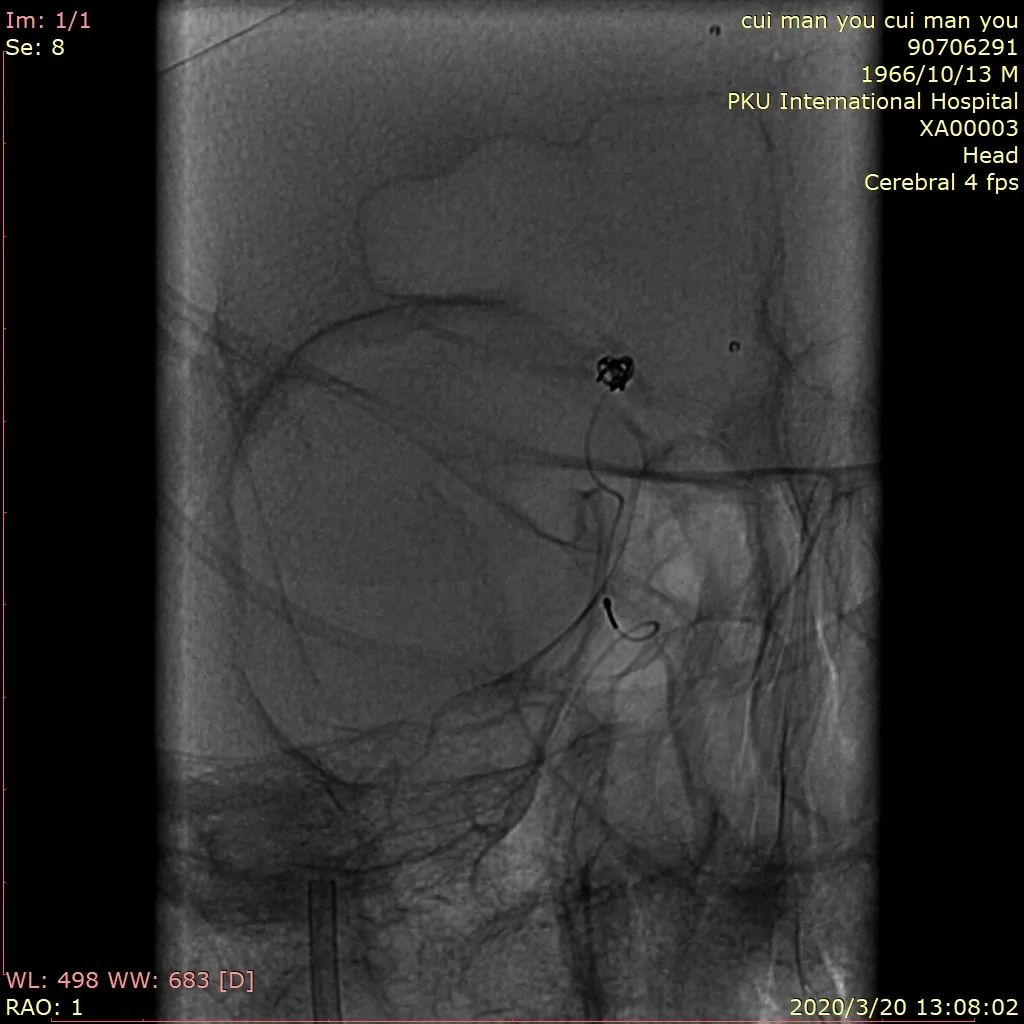

图6 最后一枚弹簧圈推送后更换角度见弹簧圈部分位于支架及血管壁之间,考虑对侧A1缺如,右侧A1重要,必须保留,撤出弹簧圈

图7 术后造影见动脉瘤不显影,分支血管及载瘤动脉通畅,支架位置可